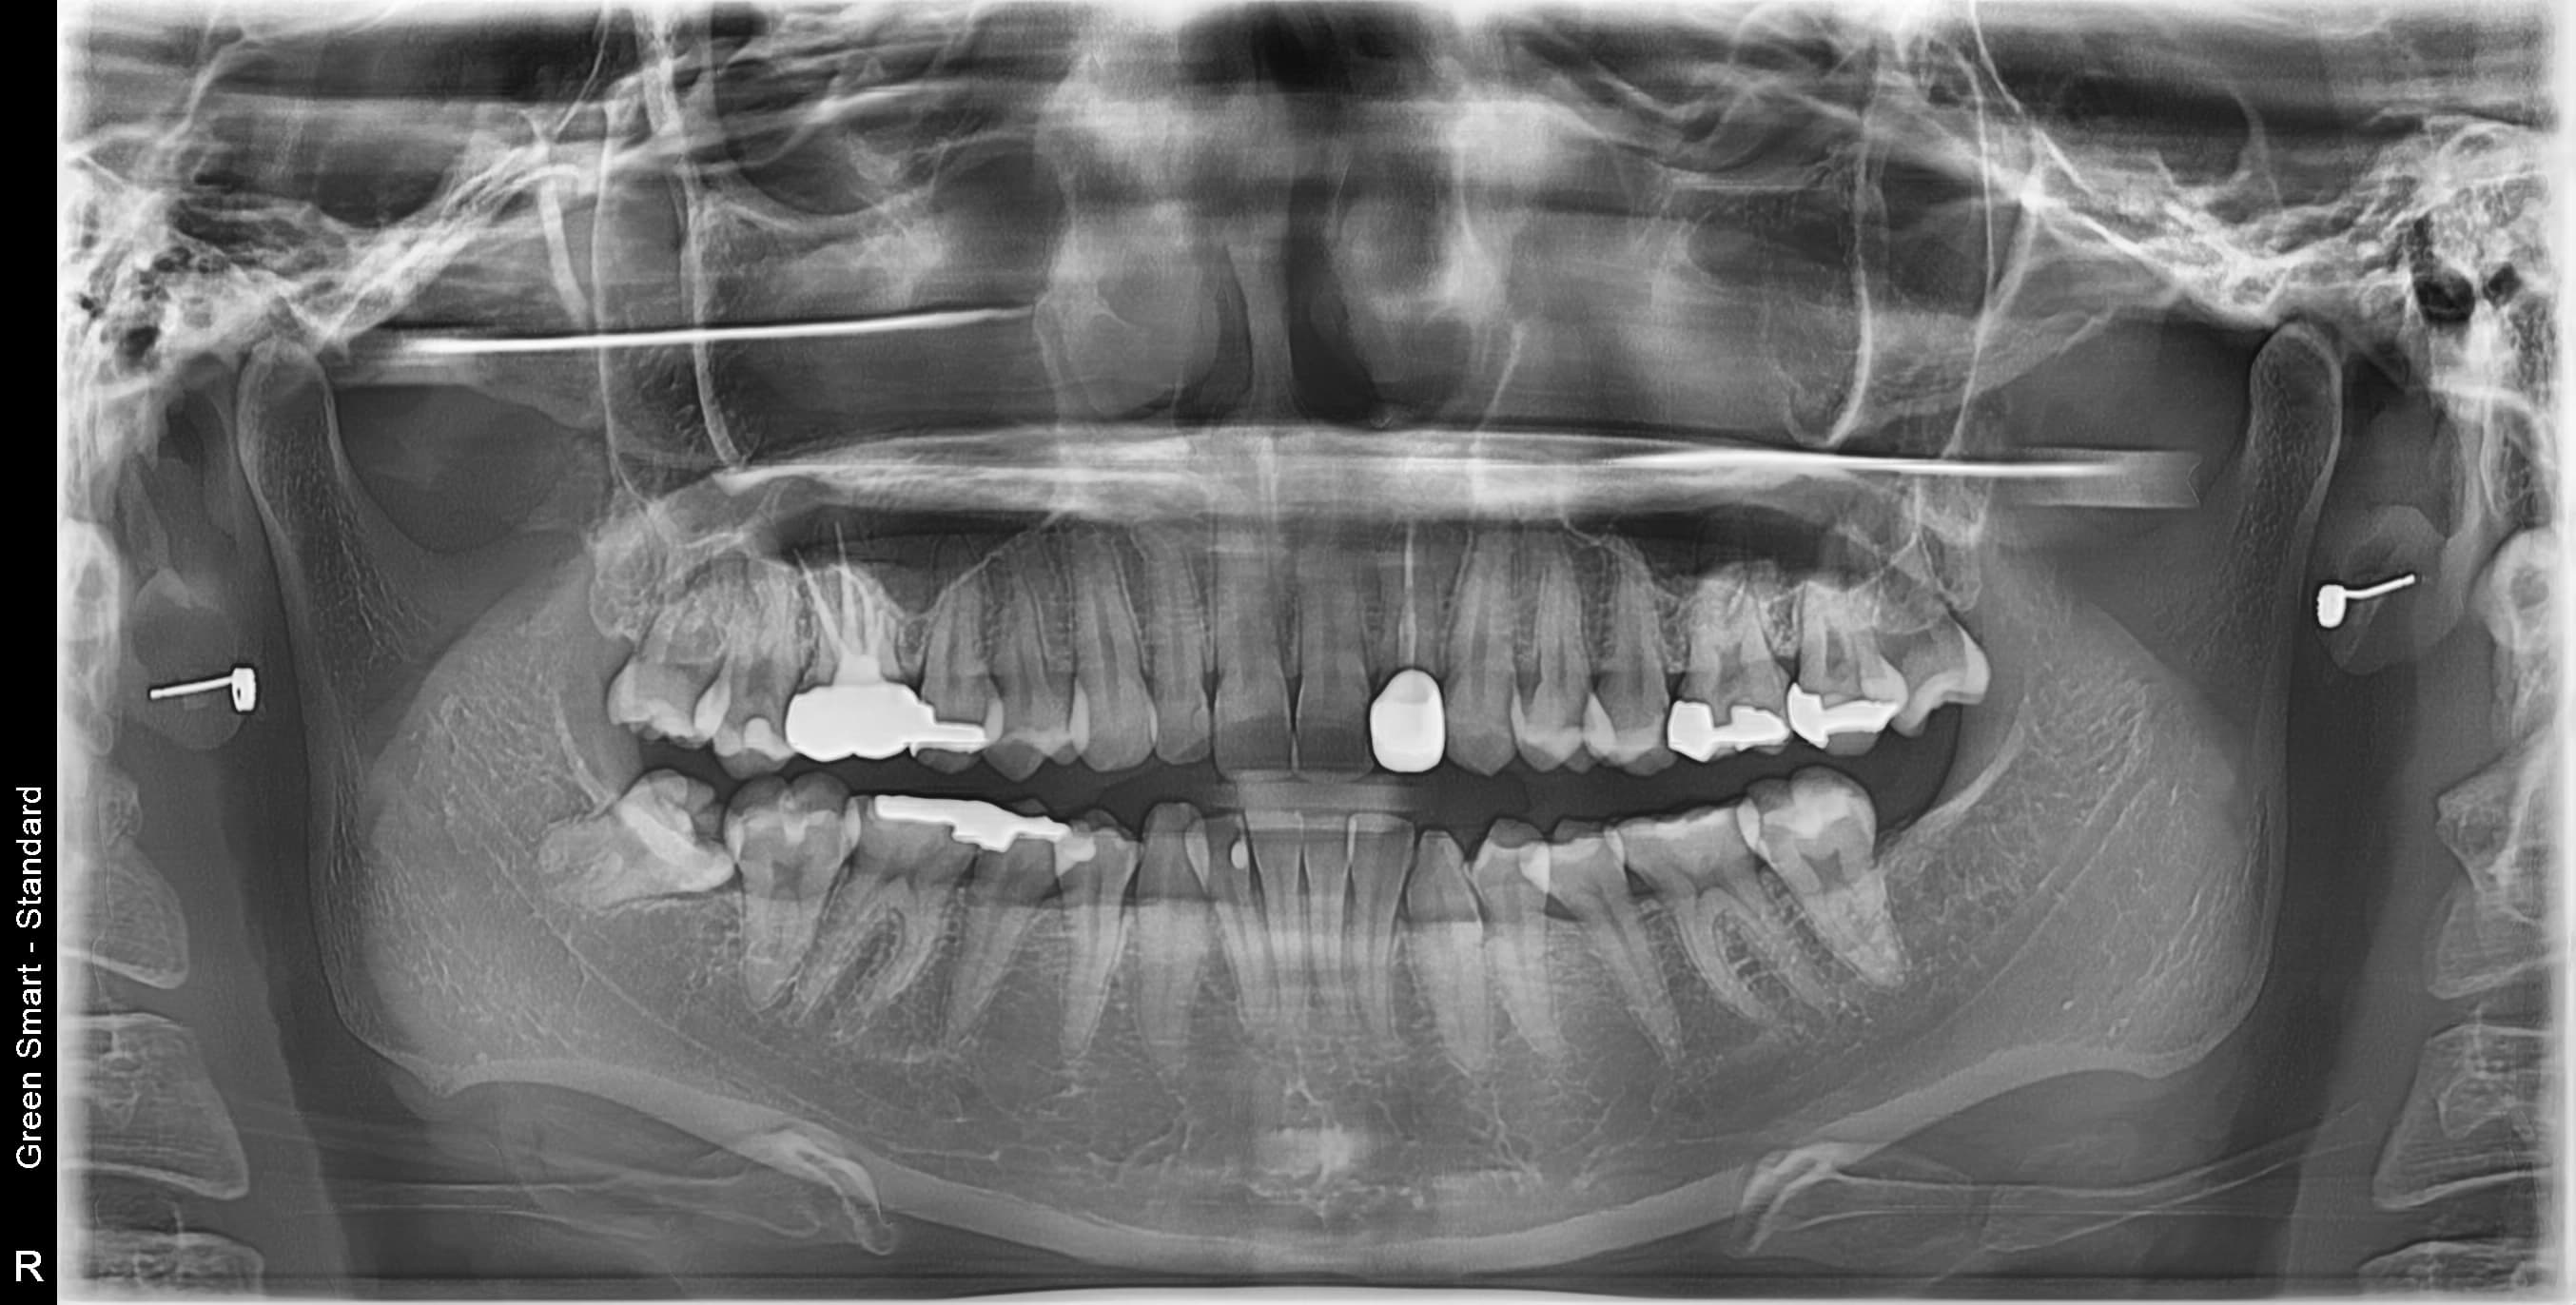

사랑니 상태별 위험도

Before

After

저위험

정상 사랑니

정상적으로 자란 사랑니도 관리가 어려워 충치 위험이 높습니다

중위험

부분매복 사랑니

음식물이 끼기 쉽고 염증이 자주 발생합니다

고위험

완전매복 사랑니

낭종 형성 가능성이 있어 조기 발치가 필요합니다

치근만곡 사랑니

뿌리가 구부러져 있어 발치 난이도가 높습니다

즉시 처치 필요

수평매복 사랑니

앞 치아를 밀어 치열 불균형과 충치를 유발합니다